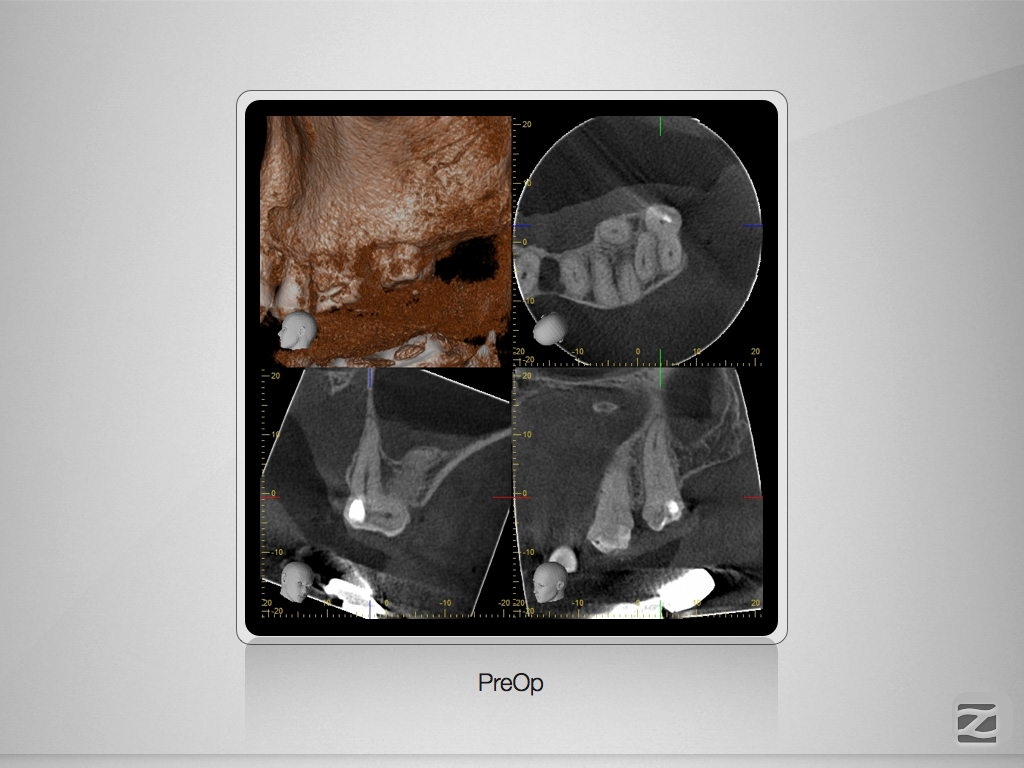

27D.001

Hyflex Fallbeispiel (3/3)